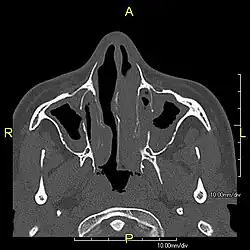

Around 80% of people with primary ciliary dyskinesia experience respiratory problems beginning within a day of birth. Many have a collapsed lobe of the lung and blood oxygen low enough to require treatment with supplemental oxygen.[1] Within the first few months of life, most develop a chronic mucus-producing cough and runny nose.[1] The main consequence of impaired ciliary function is reduced or absent mucus clearance from the lungs, and susceptibility to chronic recurrent respiratory infections, including sinusitis, bronchitis, pneumonia, and otitis media. Progressive damage to the respiratory system is common, including progressive bronchiectasis beginning in early childhood, and sinus disease (sometimes becoming severe in adults). However, diagnosis is often missed early in life despite the characteristic signs and symptoms.[2] In males, immotility of sperm can lead to infertility, although conception remains possible through the use of in vitro fertilization, there also are reported cases where sperm were able to move.[8] Trials have also shown that there is a marked reduction in fertility in females with Kartagener's syndrome due to dysfunction of the oviductal cilia.[9]

Many affected individuals experience hearing loss and show symptoms of otitis media which demonstrates variable responsiveness to the insertion of myringotomy tubes or grommets. Some patients have a poor sense of smell, which is believed to accompany high mucus production in the sinuses (although others report normal – or even acute – sensitivity to smell and taste). Clinical progression of the disease is variable, with lung transplantation required in severe cases. Susceptibility to infections can be drastically reduced by an early diagnosis. Treatment with various chest physiotherapy techniques has been observed to reduce the incidence of lung infection and to slow the progression of bronchiectasis dramatically. Aggressive treatment of sinus disease beginning at an early age is believed to slow long-term sinus damage (although this has not yet been adequately documented). Aggressive measures to enhance clearance of mucus, prevent respiratory infections, and treat bacterial superinfections have been observed to slow lung-disease progression. The predicted incidence is 1 in approximately 7500.[10]

Diagnosis

Several diagnostic tests for this condition have been proposed.[5] These include nasal nitric oxide levels as a screening test, light microscopy of biopsies for ciliary beat pattern and frequency and electron microscopic examination of dynein arms, as the definite diagnosis method. Genetic testing has also been proposed but this is difficult given that there are multiple genes involved.[6]